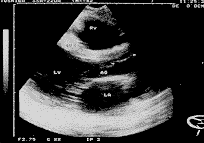

中国超声医学杂志990533 患者,男性,42岁。以往身体健康,为重劳动力。于入院前2月无原因心慌、气促、乏力,活动时明显加重,双下肢轻度水肿。近十天来病加重,来院就诊。查体:体温、脉博、呼吸均正常,血压17/7kPa。无紫绀。于主动脉瓣区可闻及粗糙Ⅲ级收缩期杂音,心界扩大。无腹水征,双下肢有轻度压陷性水肿。超声心动图检查:左室长轴切面,右室流出道35mm,主动脉舒张末期内径30mm,左房舒张期内径31.7mm,主动脉瓣开放距离20.2mm,主动脉瓣膜舒张期呈双线回声改变,间距5.4mm,收缩期在左心长轴和大血管短轴切面,右冠状瓣叶回声增强,呈锯齿状蓬草样改变(图1)。LA/AO=1.06。二尖瓣前后叶舒张期呈逆反运动,开放距离21mm。二尖瓣前叶舒张期为双峰,回声增强,增粗呈草蓬样改变。在E、A峰前显示蓬乱异常条索状反射,收缩期消失(图2)。CD段稍凹陷。左室流出道54.8mm,左室舒张末期内径77mm,左室收缩期内径54.1mm。二维超声心动图:左室长轴切面:主动脉右冠瓣舒张期线条状强回声脱入左室流出道(图3),收缩期又返回到主动脉腔(图4),呈梿枷样活动往返于左室流出道与主动脉腔之间。超声诊断:主动脉瓣膜撕裂。

图3 舒张期主动脉瓣膜脱入}

左室(箭头所指)

讨论:主动脉瓣膜撕裂较为少见,其病因可能由于感染性心内膜炎瓣膜破裂所致。临床很难作出诊断。超声心动图对本病有特殊表现的声像图,具有特异性诊断价值其特征主要是在左室长轴切面上显示主动脉瓣膜在舒张期脱入左室流出道,且超过主动脉瓣环附着点连线以下,收缩期又返回到主动脉腔内,呈梿枷样往返运动。M型超声心动图:心脏舒张期,二尖瓣前叶E、A峰前出现蓬乱异常回声。此异常回声为主动脉闭锁不全血液返流冲击脱垂的主动脉瓣膜所引起。